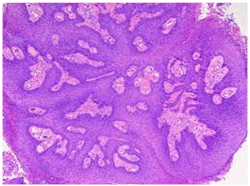

Histopathological statutes: The squamous epithelium displays finger like projections, the epithelial maturation pattern is orderly with epithelial hyperkeratosis. Spinous epithelial cells may depict cytoplasmic vacuolation with pale, clear perinuclear haloes, nuclear pyknosis and infrequent basilar hyperplasia. Oral squamous papillomas frequently display koilocytosis on account of the co-existent cytopathic influence. Atypical nuclear alterations may be exemplified; particularly with immune-compromised (HIV positive) individuals.9 The epithelium displays a typical maturation pattern with prominent hyperkeratosis. Epithelial to basal cell quantification is moderate (basilar hyperplasia) along with an extensive koilocytic transition.1 Virally induced carcinomas are the poorly differentiated, non-keratinizing tumours and may be enunciated in the tonsils of sexually active young men. Majority of the tumours elucidate the p16 proteins. Oro-pharyngeal cancers which are reactive for human papilloma virus (HPV) frequently depict basaloid morphology. Apart from a viral genesis, squamous papillomas may ensue from mechanical irritation or may be genetically determined as a constituent of Cowden’s syndrome.

Figure 5 Inverted Papilloma with epithelial hyperplasia.

Figure 7 Papillomas with buried epithelial glands.